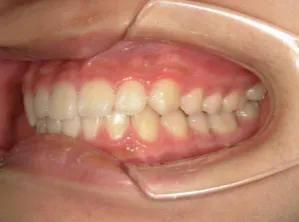

治療後⑧小6(12y3m):モノブロック装置継続中

治療後⑨中2(13y11m):モノブロック装置継続中

咬み合せも安定していて、口元の突出・口唇閉鎖不全も改善

*レントゲンや歯の萌出状況などから成長が終了していると考えられるため、現在残っている隙間や上下正中の不一致を改善するためマルチブラケット法へ移行するか検討中です。

治療は歯並びや口元などの状態から非抜歯治療で行う予定です。